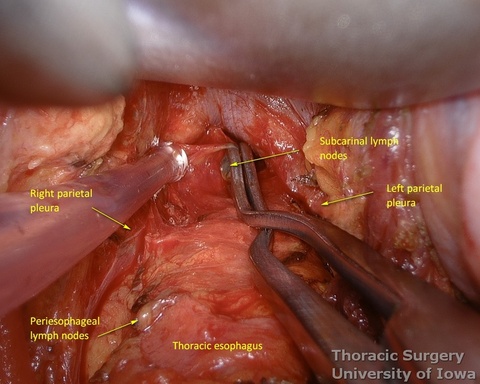

- Esophagus is circumferentially mobilized under direct vision using combination of sharp and blunt dissection up to the level of the carina.

- Right lateral esophageal “ligament” (attachments to the parietale pleura, pulmonary ligaments and branches of vagal nerves) is exposed are divided under direct vision

- Left lateral esophageal attachments (“ligament") is divided under direct vision

- Periesophageal and subcarinal lymph nodes are dissected separately or en-block with the esophagus under direct vision.

- Dissection of the distal and mid esophagus is completed using a combination of an energy device and suction tips.

- Through the abdomen, the hiatus is enlarged to allow a hand entry. Circumferential midesophageal and proximal esophageal dissection is gently completed in the superior mediastinum with fingers sequentially through the neck incision (along with gently traction on the cervical esophagus) and hiatus (along with gently traction on the Penrose around the gastroesophageal junction).